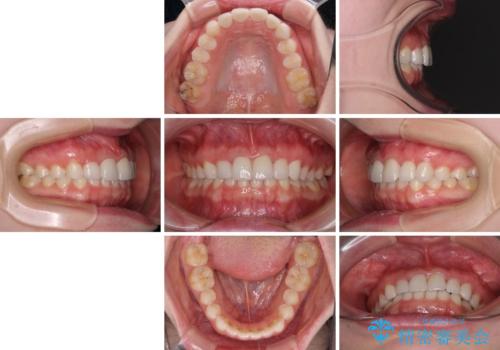

上下前歯の歯列不正はインビザラインにより歯列を整え、その後に、前歯5本をオールセラミッククラウンにて補綴治療することとしました。

矯正治療にて歯並びを整えた後に、虫歯の大きかった5本の歯をセラミッククラウンにて補綴し、明るい口元になりました。